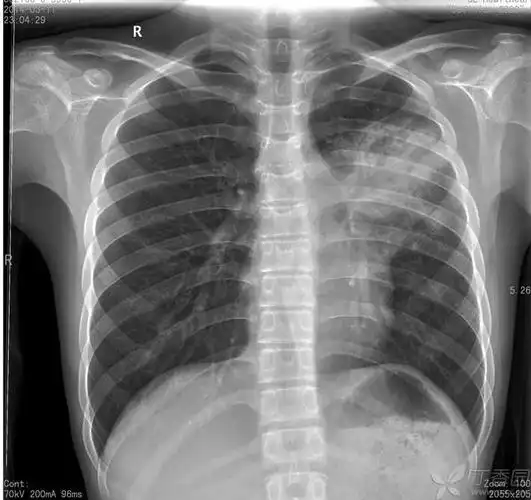

于2014-02-27拍胸片,诊断为大叶性肺炎; 在当地诊所抗炎治疗,10天左右